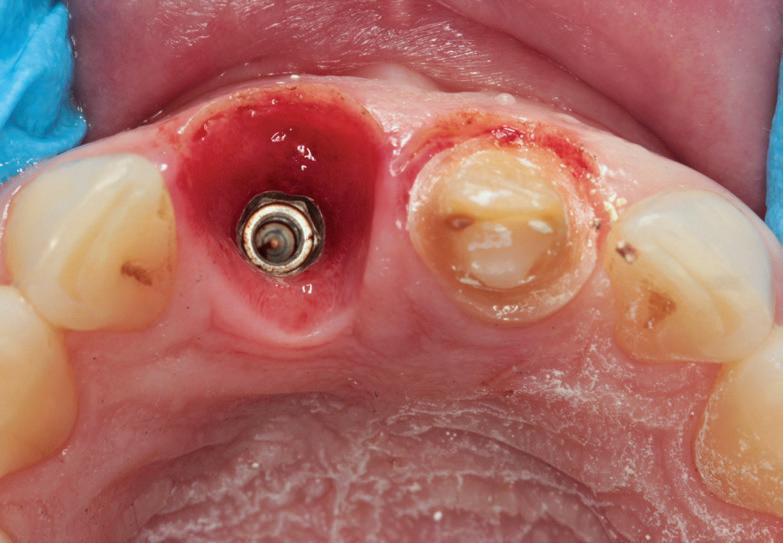

Totuși, ca și în cazul implanturilor de titan, în rare cazuri, și la cele ceramice poate apărea o recesie nedorită cu expunerea umărului implantar. Cu toate acestea, din punct de vedere estetic, această recesie a gingiei inflamate este posibil să fie mult mai bine tolerată de către pacienții preocupați de marginile întunecate ale implanturilor de titan (fig. 2).

Trebuie remarcat, totuși, că în cazul implanturilor ceramice, ca și în al celor de titan, cementita, adică inflamația periimplantară cauzată de reziduurile de ciment, poate duce la periimplantită. În plus, la implanturile din dioxid de zirconiu poate apărea supraîncălzirea la înșurubarea implantului în os, iar suprafețele excesiv de aspre sau poroase ale implantului pot cauza defecte osoase periimplantare din cauza termoconductivității reduse a materialului. Deși sunt necesare mai multe dovezi științifice care să demonstreze o tendință mai scăzută spre periimplantită în cazul implanturilor ceramice, argumentul esențial pentru aceste implanturi bazat pe experiența clinică este starea excelentă și aproape constant lipsită de inflamație a țesuturilor moi periimplantare (fig. 3).

1. Implanturi din titan (stânga) și zirconiu (dreapta). 2. Recesii la implanturile ceramice (stânga) și din titan (dreapta). 3. Țesut moale cu implant din zirconia, lipsit de inflamație.